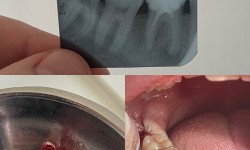

Видалення зубів мдрості

Безболісне видалення зубів мудрості/вісімок